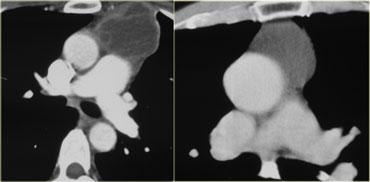

CT cho thấy một khối nằm ở trung thất trước.

Khối có dạng nang nhưng có các vách ngăm thuốc cản quang dạng đặc.

Đây là dấu hiệu rất đặc trưng của u tế bào mầm.

Nhiều người cho rằng u tế bào mầm phải chứa mỡ và nếu tổn thương không chứa mỡ thì không thể là u tế bào mầm.

Cần nhớ rằng chỉ khoảng 60% u tế bào mầm có chứa mỡ, do đó sự vắng mặt của mỡ không loại trừ u tế bào mầm khỏi chẩn đoán phân biệt.

Thành phần đặc càng nhiều thì khả năng u tế bào mầm ác tính càng cao.